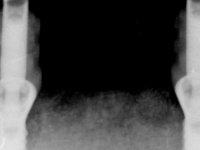

After clinical and radiological evaluation several rehabilitation plans were discussed with the patient. It was decided to extract the remaining lower teeth and do an overdenture retained by two dental implants with the locator attachement system to achieve a better retention and stabilization of the lower denture.

Two dental implants were planned in the CBCT scan, in the area of the inferior canines. The dental extractions were performed and, simultaneously, the alveolar crest was flattened and the implants were placed. Three issues were considered while implant placement: parallelism of the axis, same height of the implant’s neck, and same position in the coronal plan. This 3D insertion is essential to have a good retention of the overdenture in the future. Patient’s removable denture was fixed in the dental lab, to include the extracted teeth, and a soft-tissue relining was done over the healing abutments. After the osseo-integration period, a first impression was done with an open-tray and a doble-mix technique. This dental impression allowed the production of screwed wax-rims and an individual tray for a functional impression. A second impression, final, was done with an individual tray with a monophasic silicone. The occlusal wax-rims were correct in the mouth according to the full denture guidelines. Special care was taken with the occlusal vertical dimension and the support in the soft-tissues. A silicone bite registration material was used to better defined the intermaxillary relations. Teeth set-up was done in the dental lab with the selected tooth color. Due to the fact that the base was screwed to the dental implants, the teeth set-up was functionally evaluated in the mouth. Another silicone bite registration material was used to allow final occlusal adjustments. Finally, the locators were screwed and the retention nylons were selected according to the patient needs.